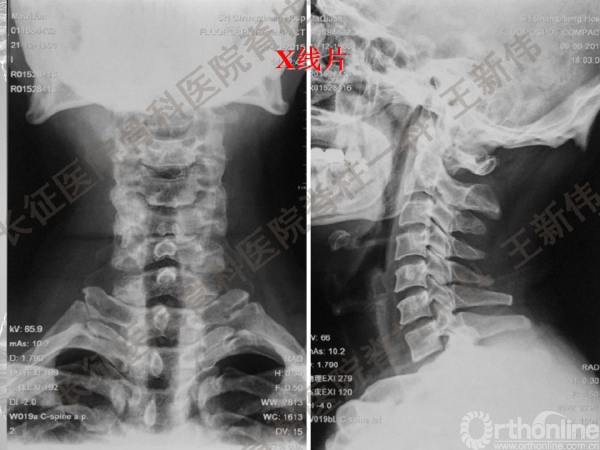

王新伟:颈椎后路通道下手术病例报告及文献回顾

颈椎后路通道下手术有哪些?颈椎后路通道下手术能做哪些事?颈椎后路通道下手术有哪些优势?长征医院骨科医院脊柱一科王新伟副教授通过临床病例报告及文献回顾,给出了他的答案——